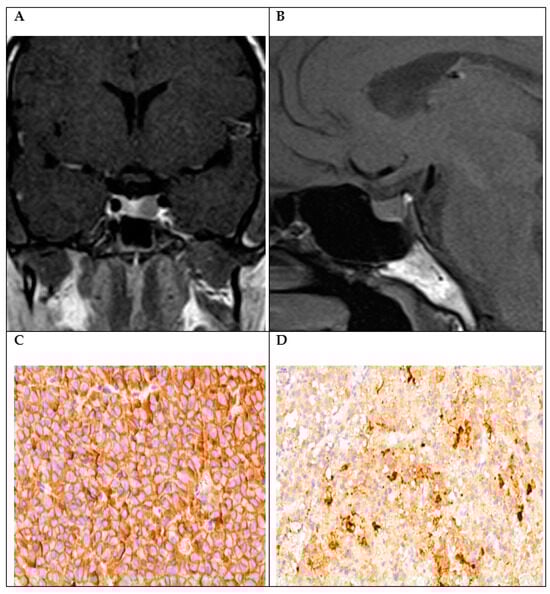

| 2 | GH + LH | +3 | 0 | +1 | <3% | Perinuclear (densely granulated) | Acromegaly | No |

| 3 | GH + LH | +3 | 0 | +3 | <3% | Perinuclear (densely granulated) | Acromegaly | No |